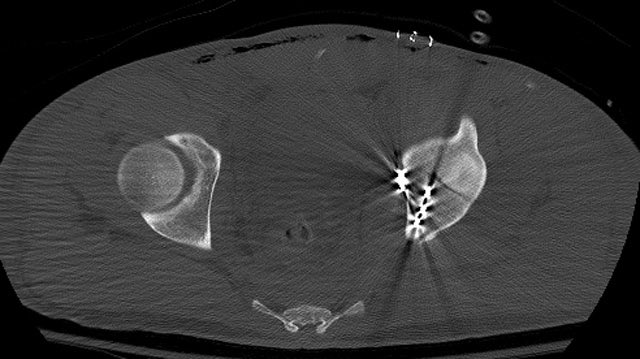

The axial dome image

The postop CT helps us assess and understand the articular reduction and implant applications best